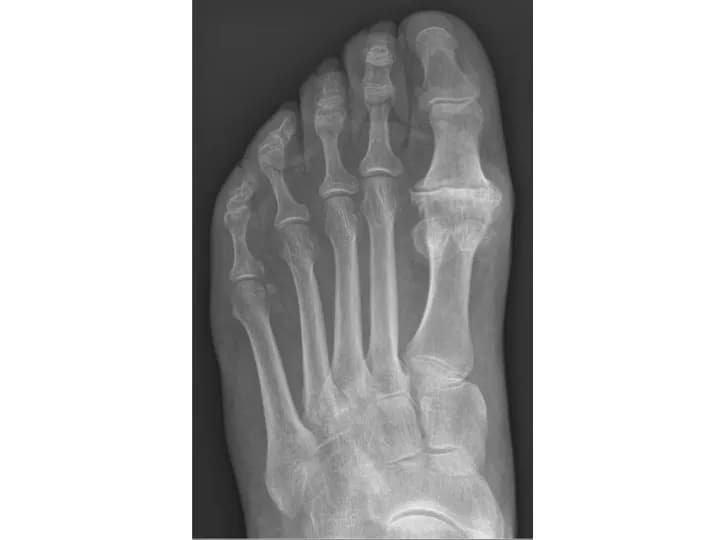

Hallux Rigidus (or Stiff Big Toe) is a degenerative form of arthritis that can cause pain and stiffness to the joint; chiefly the metatarsophalangeal (MTP) joint, at the base of the big toe. Test your knowledge of this medical condition by taking our quiz!